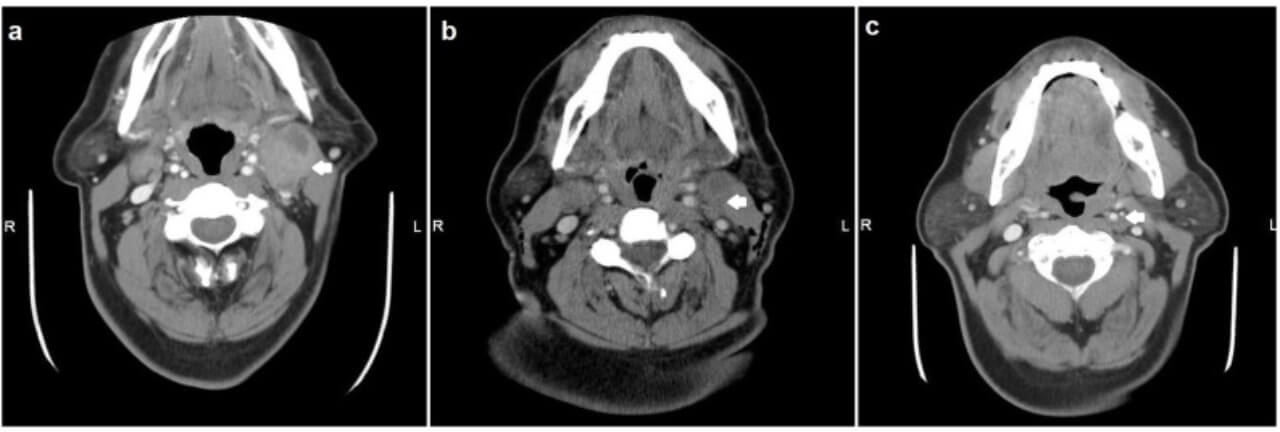

- Computed tomography (CT scan). With the help of X-rays, doctors get images of the tumour and scan for possible spread to other organs, like the lungs.

Take the case of a 47-year-old man who was diagnosed with a stage 4 aggressive tumour at the base of the tongue [10]. He started treatment in one of the best oral cancer treatment centers in Germany with the intra-arterial chemotherapy via the left and right carotid arteries. This allowed him to avoid the surgery that would have taken away his ability to eat and speak. But after three cycles of isolated thoracic perfusion with chemofiltration, the scans showed no visible tumour. And now, more than four years later, he enjoys his active, normal life in complete remission.